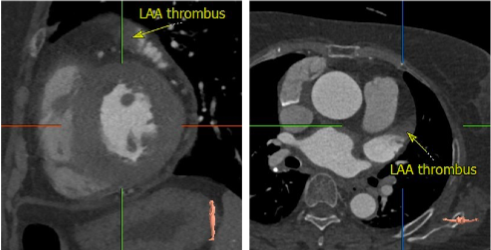

该病例为70岁女性患者,间歇胸闷气短17年,反复住院药物保守治疗,效果不佳,10日前症状加重,伴有胸痛、头晕、黑朦,双下肢水肿,转于我院就诊。经检查分析,诊断为重度主动脉瓣狭窄,风心病,患者主动脉瓣叶增厚,左心耳血栓,左冠开口小于10mm,存在一定冠脉阻塞风险,右侧股动脉分叉在股骨头中点,左侧股动脉分叉高于股骨头中点,双侧髂外动脉最小直径小于5.5mm,主动脉弓角偏大,对血管介入造成难点,同时易引起血管并发症,手术难度大。经杨毅宁教授团队充分评估,对患者采取全麻下经食道超声监测,选用目前行业最低入路要求美敦力递送系统配合自带内联鞘进行介入。

根据术前CT分析,结合患者瓣膜钙化情况,决定预装Evolut PRO 26mm瓣膜,采用超声引导下穿刺,确保入路精准,对血管损伤最小。